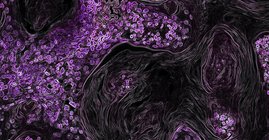

Wie unterscheiden sich krebskranke von gesunden Zellen? Ein neuer Machine-Learning-Algorithmus namens „ikarus“ kennt die Antwort, berichtet ein Team…